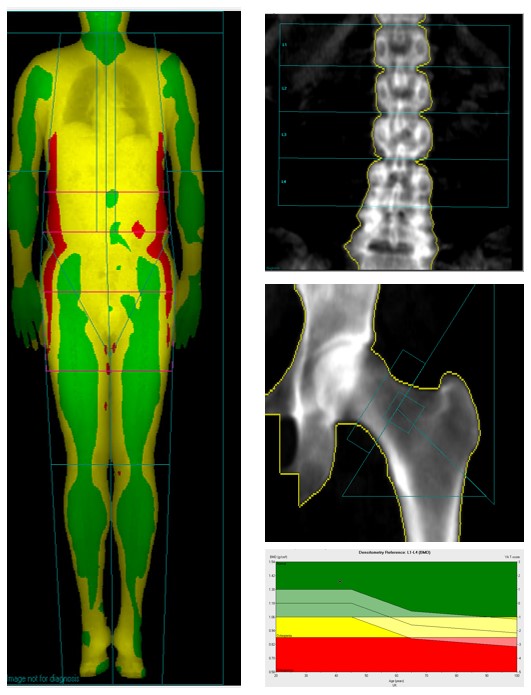

DXA BMD and Body Composition

Dual-Energy X-ray Absorptiometry (DXA) is a diagnostic technique crucial for evaluating bone health by measuring bone mineral density (BMD) while Body Composition analyses the overall body makeup, examining the proportions of fat, lean tissue, and bone.